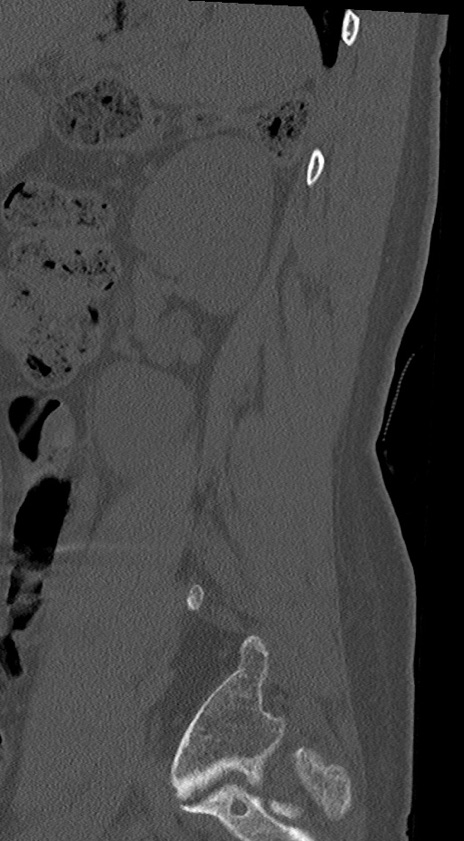

【整形】TIPS症例4 腰椎CT(矢状断像)

腰椎CT

冠状断像